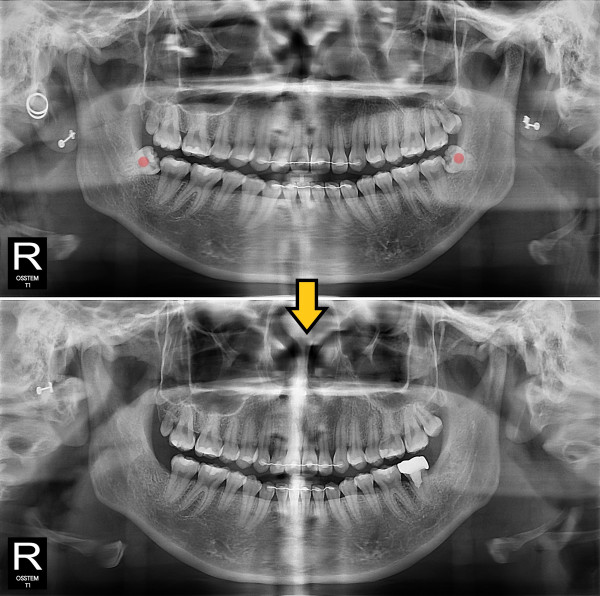

사랑니발치 충치가 심한 사랑니

ae27575af29d49719312fde5a1f0cca6_1764401999_3547.jpg